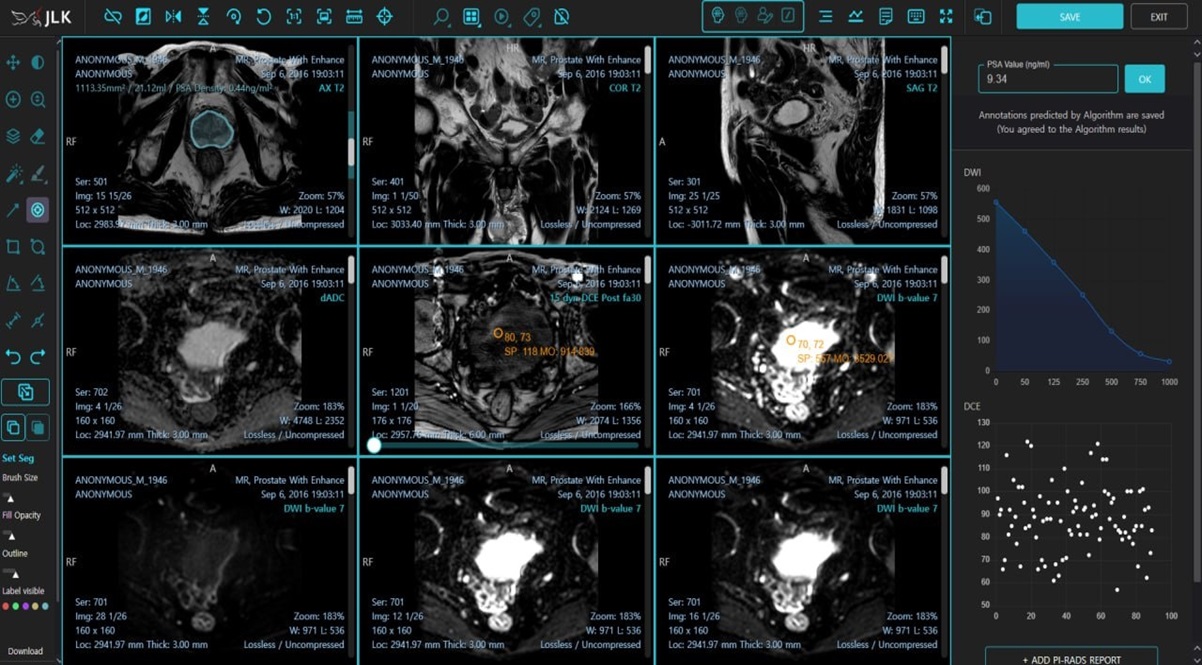

제이엘케이는 서울아산병원, 미국 미주리대학교와의 임상시험으로 전립선암진단 AI 솔루션을 개발, FDA에서 승인 받았다고 전했다. 메디허브 프로스테이트는 AI를 활용해 다중 매개변수 전립선 MR 영상을 복합적으로 분석, AI가 PIRADS(암 의심 정도를 나타내는 지표) 진단 및 PSA(전립선 특이 항원) 등 진단에 필요한 모든 데이터를 제공한다.